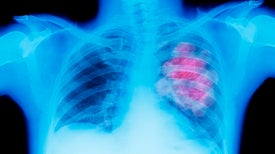

Handheld Ultrasound Devices Are Speeding Diagnosis of COVID-19

Doctors can triage and monitor patients faster—and sometimes more accurately—with the aid of the pocket-size machines